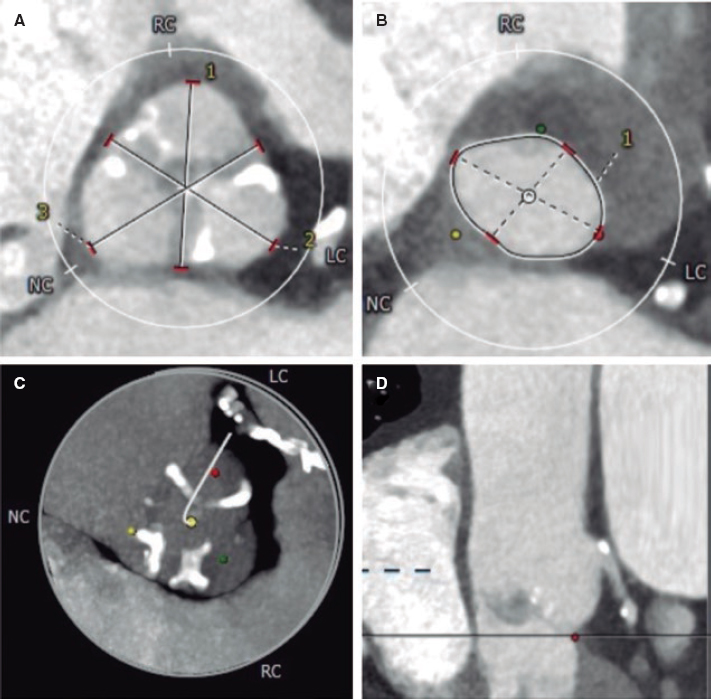

The intravascular ultrasound (IVUS) is useful when the entry site is ambiguous and there are no references to position the guidewire. A lateral branch is required to place the guidewire and IVUS. In these cases, the Slipstream technique38 is very useful. It consists in placing a dual-lumen micro-catheter (DLM) behind the IVUS above the branch guidewire. This increases tremendously the strength exerted with the guidewire that exits the DML lateral port providing better torque and grip (figure 3). The IVUS shows where the occlusion of the vessel is in order to navigate the guidewire (of high-gram, directivity, and torque-response) towards that point (figure 4).

Figure 3. The occluded vessel is at the 6 o’clock position approximately (A) as the guidewire is moving towards the occlusion (B, C and D).

Figure 4. The catheter of intravascular ultrasound in the subintimal space is between the 9 and 12 o’clock positions and true lumen between the 3 and 9 o’clock positions.